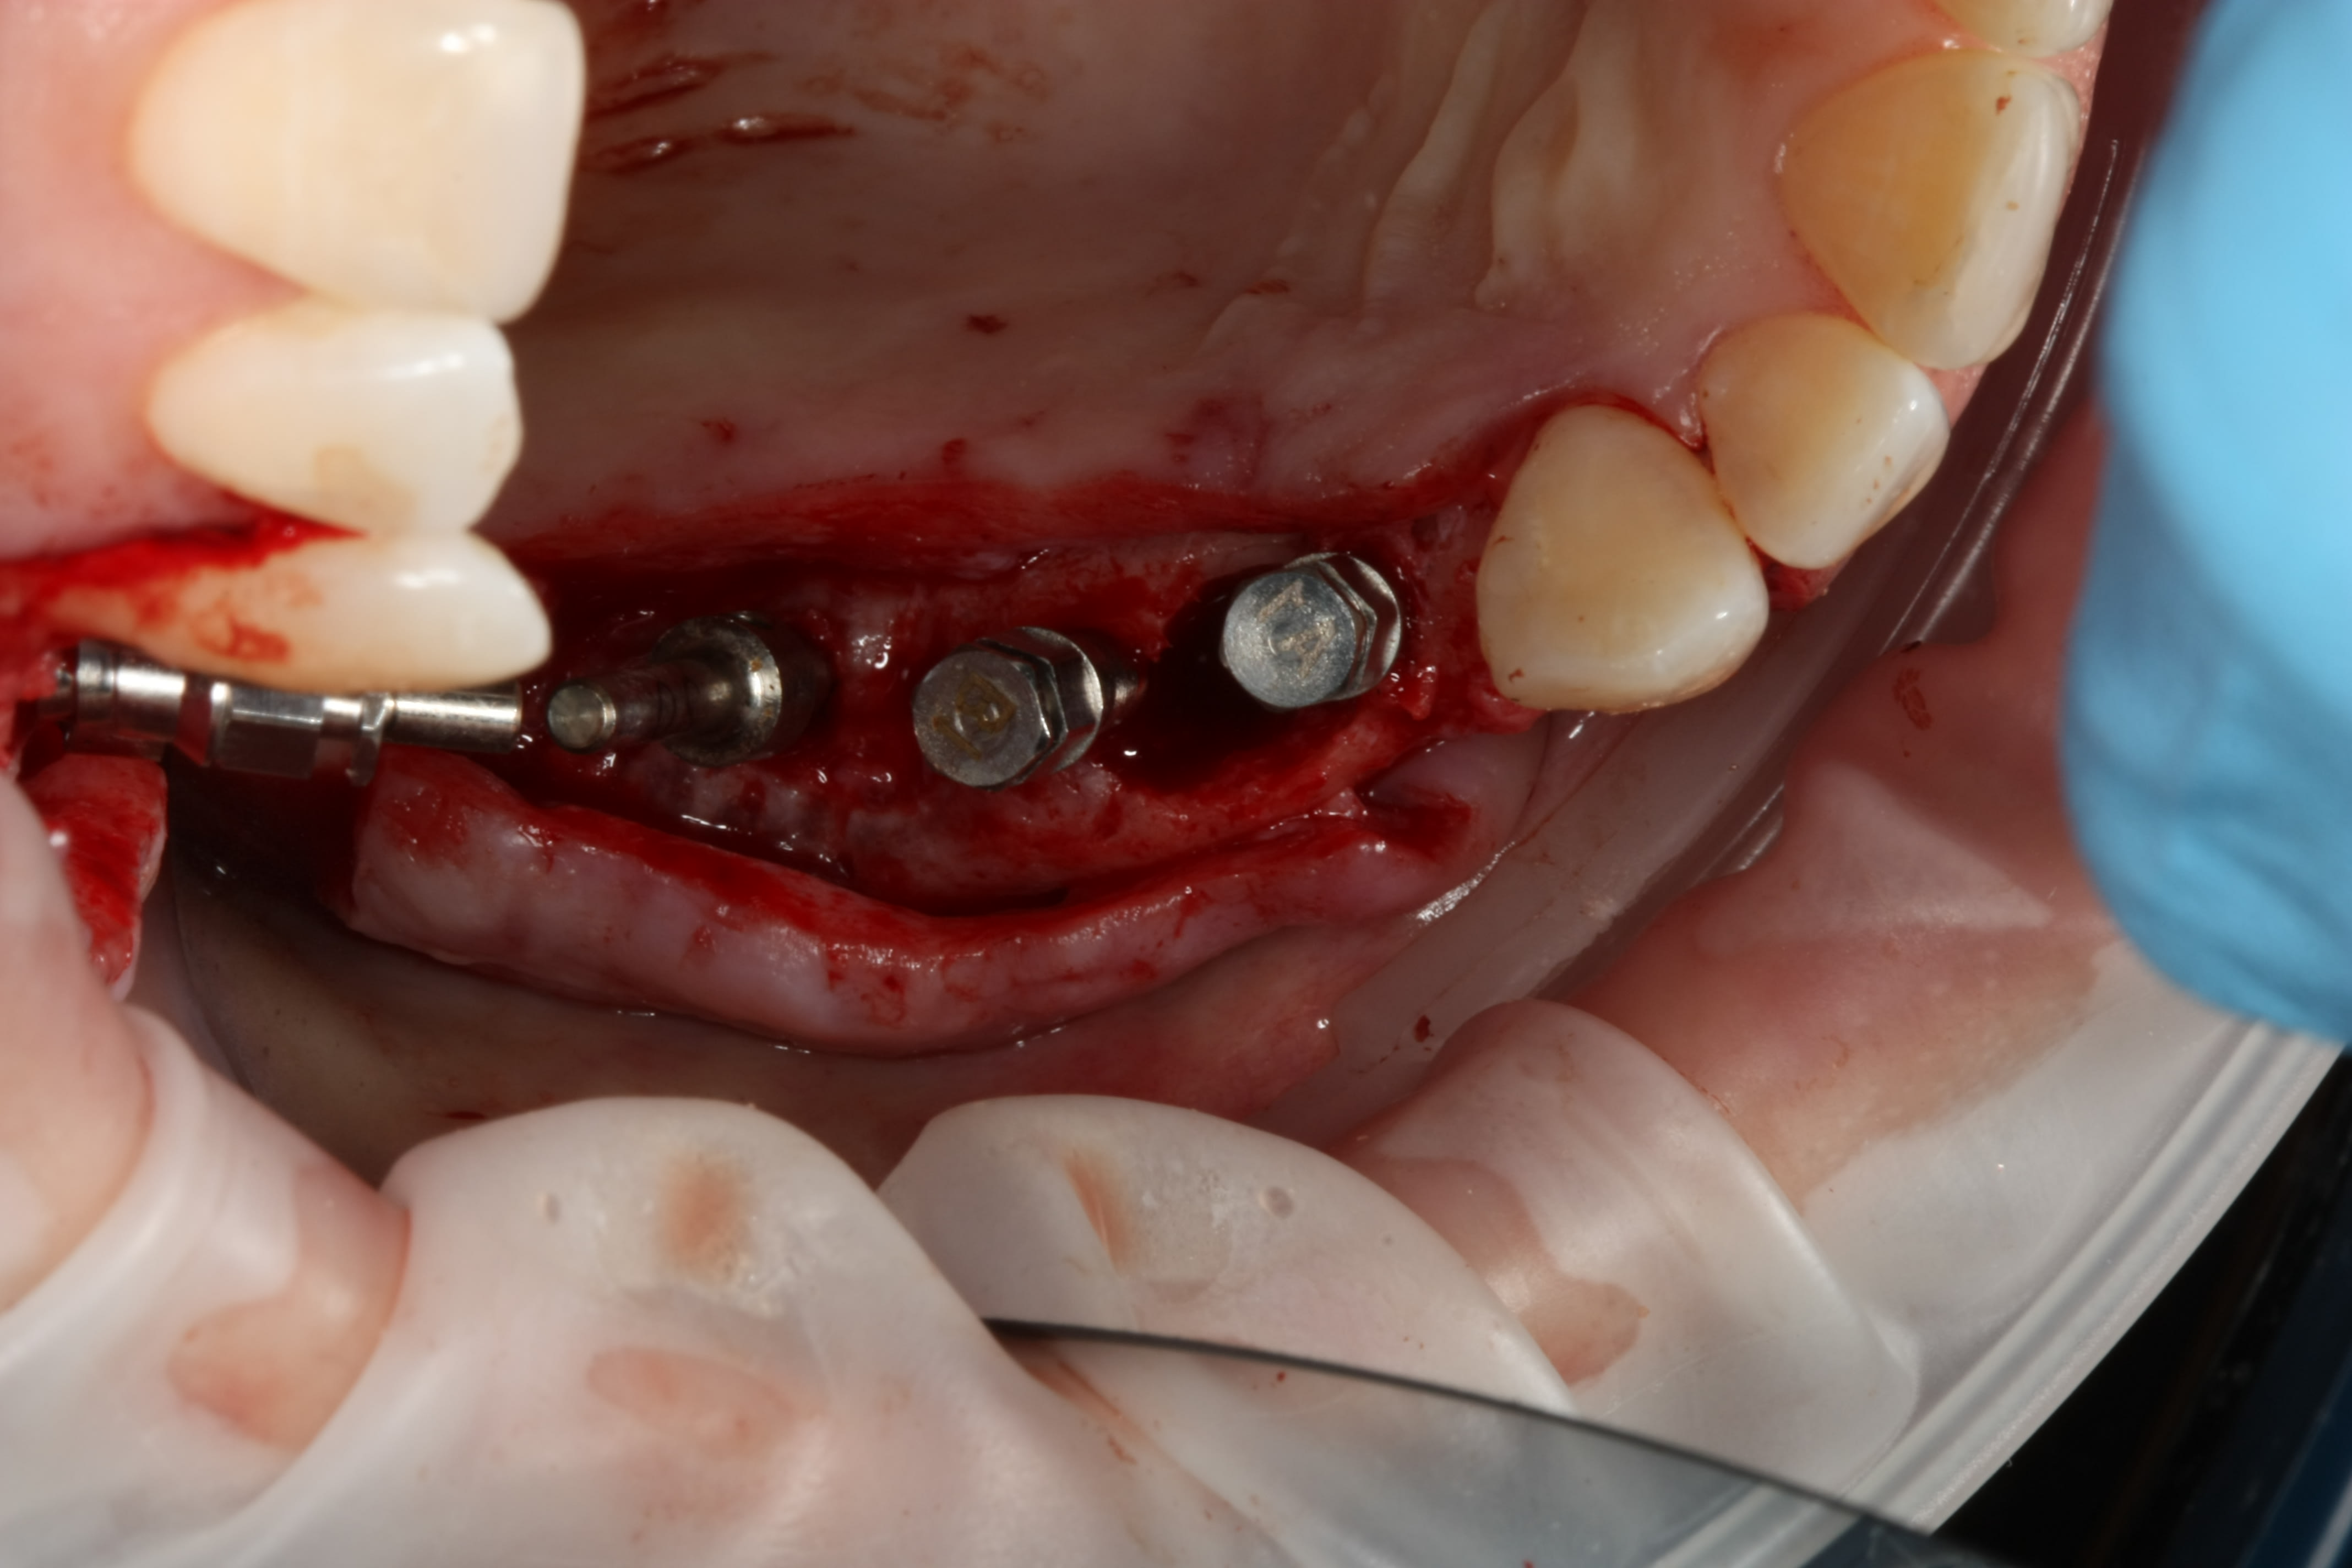

Pose implants 14-15-16 (il n'y a pas de 7 en bas)

Nobel ASC : Angle Screw Chanel pour la 14, car axe pas top

15 et 16, piliers inclus avec l'InterActive

14 Pilier ASC de chez Nobel, compatible InterActive, avec rattrapage jusqu'à 25 degrés